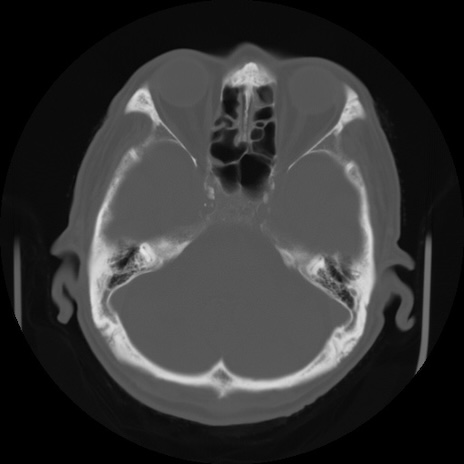

CT(冠状断像)